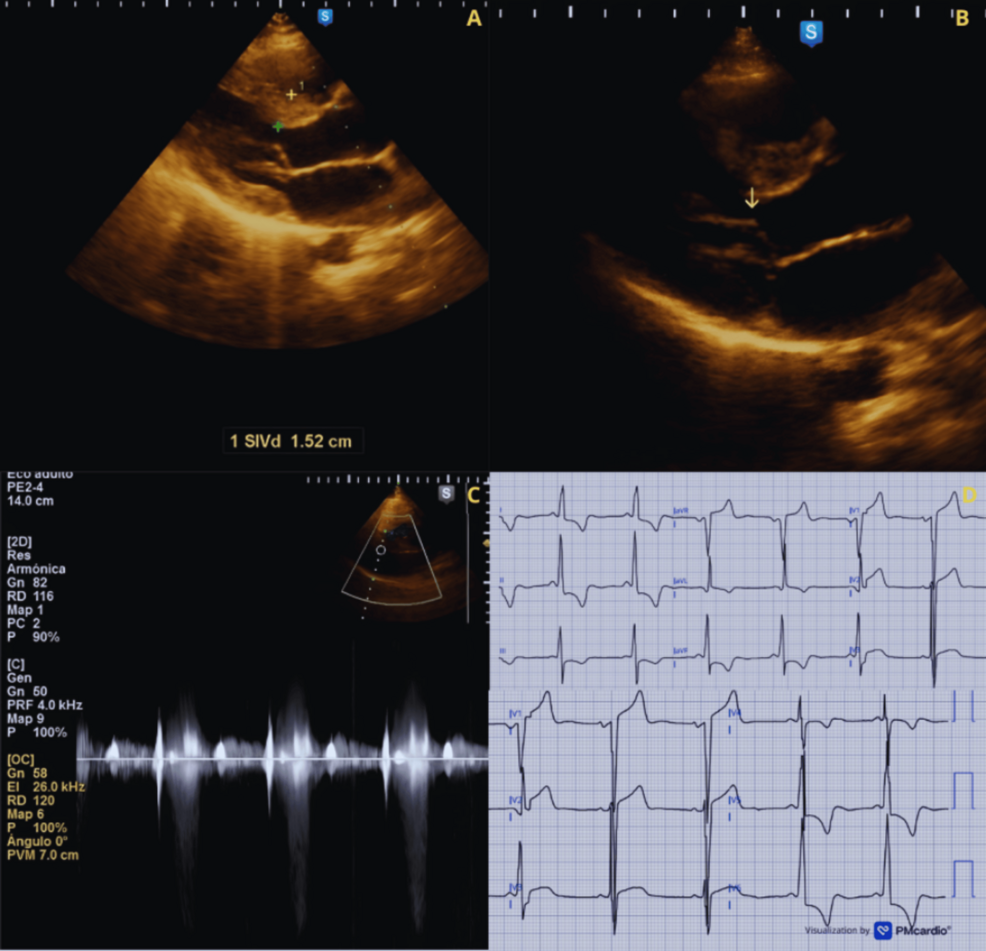

Case Report 1: Acute Heart Failure in the Third Trimester

Our first case involved a 32-year-old woman with a known diagnosis of HOCM, well-managed with beta-blockers prior to conception. she presented at 36 weeks gestation with progressive dyspnea, orthopnea, and lower extremity edema. Echocardiography revealed a significantly increased left ventricular outflow tract gradient (80 mmHg at rest, up from 30 mmHg pre-pregnancy) and moderate mitral regurgitation.

The patient delivered a healthy infant via Cesarean section at 38 weeks.Postpartum,her hemodynamics stabilized,and the left ventricular outflow gradient decreased. This case highlights the importance of proactive monitoring and prompt intervention in HOCM patients during pregnancy.

Case Report 2: Syncope and Arrhythmia in the Peripartum Period

The second case presented a 28-year-old patient diagnosed with HOCM during her first pregnancy. She experienced two episodes of syncope in the peripartum period (within 24 hours of delivery). holter monitoring revealed frequent premature ventricular contractions (PVCs) and a non-sustained ventricular tachycardia.

* echocardiogram: Showed apical hypertrophy and a dynamic outflow obstruction (60 mmHg).

* Cardiac MRI: Confirmed the diagnosis and ruled out other causes of syncope.

* Echocardiography: Remains the cornerstone of diagnosis and assessment of outflow obstruction. Serial echocardiograms are recommended throughout pregnancy to track changes in the gradient and mitral regurgitation.

* Cardiac MRI: Provides detailed anatomical and functional information, particularly useful for characterizing the type of HCM and assessing myocardial fibrosis.

* ECG: Regular electrocardiograms can identify signs of left ventricular hypertrophy or arrhythmias.